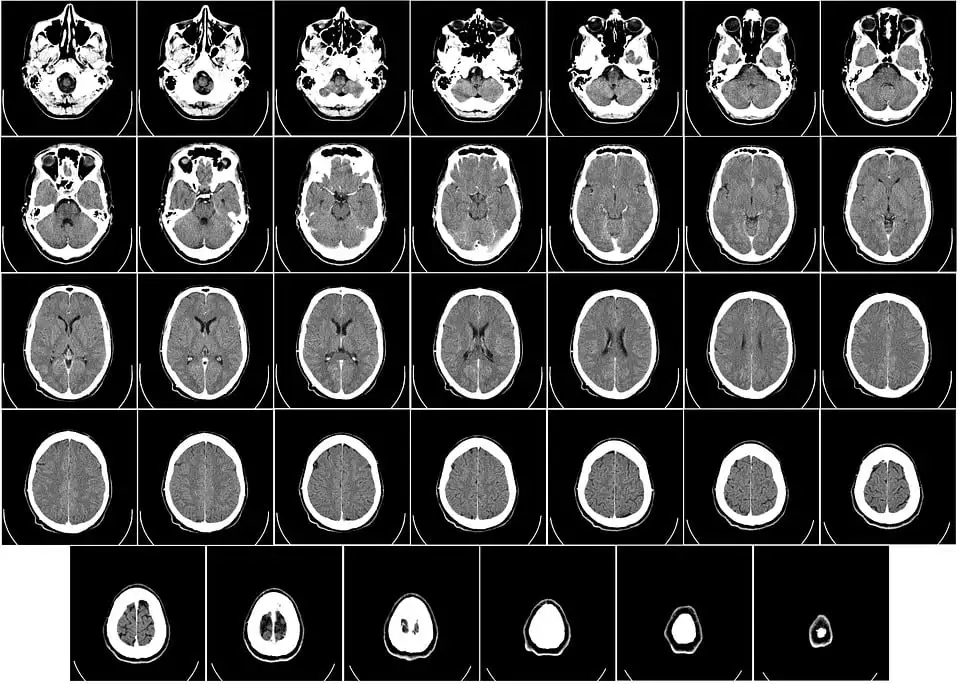

Hatta beyin kanseri için CT scan ekledim. Lazım olur.